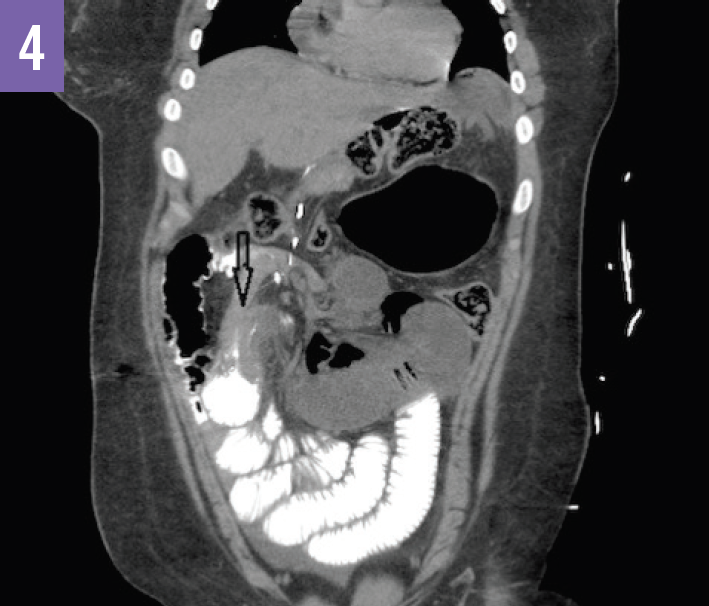

Diagnostic tests. An acute abdominal radiograph series was unremarkable for pneumoperitoneum but demonstrated a gastric air bubble (Figure 1). Computed tomography (CT) of the abdomen and pelvis with oral diatrizoate meglumine and diatrizoate sodium solution contrast medium demonstrated free air under the left hemidiaphragm and gastric pneumatosis (Figure 2), possible obstructions of the bilioenteric limb and within the common channel (Figures 3 and 4), and fat stranding at the pancreatic head (Figure 5).

Based on the imaging results, the patient received a diagnosis of internal hernia with perforation of the gastric remnant.